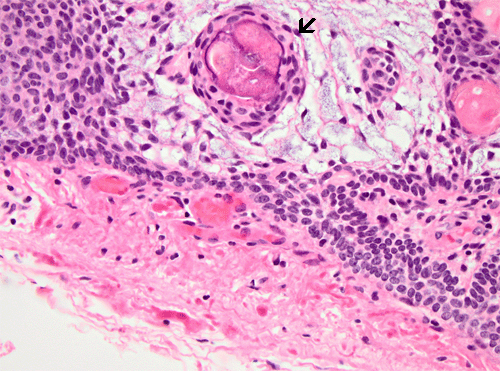

Craniopharyngioma, HE: Low and high magnification of an adamantinomatous type of cranipharyngioma. Note the presence of microscyst formation, wet keratin pearls (arrow) and the stellate cells around the keratin pearls.